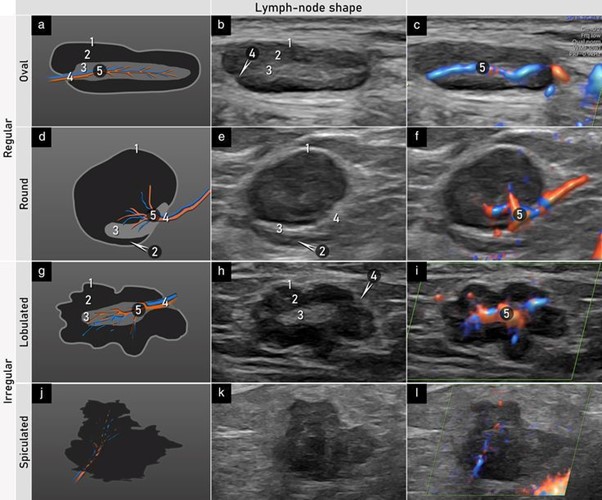

A great reference for lymph node assessment which helps standardized ultrasound terminology and measurements for lymph nodes. This provides clear guidance on describing size, shape, cortex, hilum, and vascularity.

obgyn.onlinelibrary.wiley.com/doi/10.1002/uo…